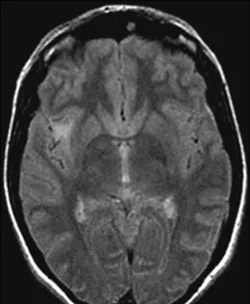

我的故事充满遗憾,愿你们不会重蹈我的覆辙。我是一名43岁的女建筑师,遗憾的是,我能精心构筑建筑,却未能构筑好自己的人生却错失了脑瘤治疗的合适施工期。 就在手术的6年前,我偶然...